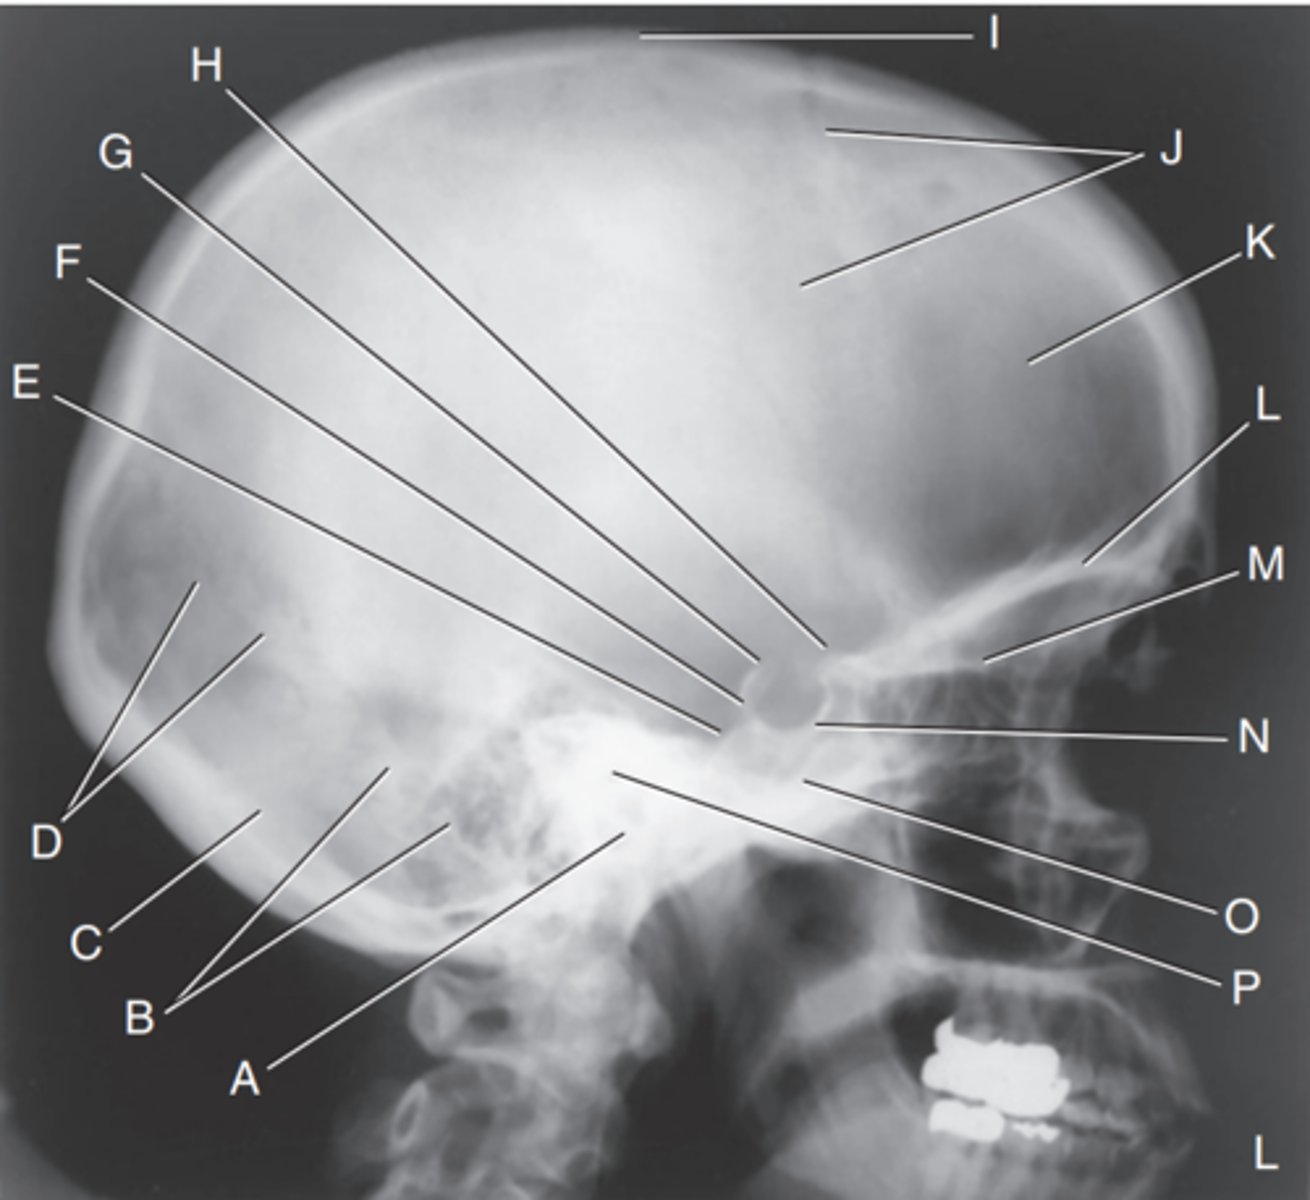

EAM

Label A

Mastoid portion of temporal bone

Label B

Occipital bone

Label C

Lambdoidal suture

Label D

Clivus

Label E

Dorsum sellae

Label F

Posterior clinoid processes

Label G

Anterior clinoid processes

Label H

Vertex of cranium

Label I

Coronal suture

Label J

Frontal bone

Label K

Orbital plates

label L

Cribriform plate

Label M

Sella turcica

Label N

Body of sphenoid (sphenoid sinus)

Label O

Petrous portion of temporal bone

Label P